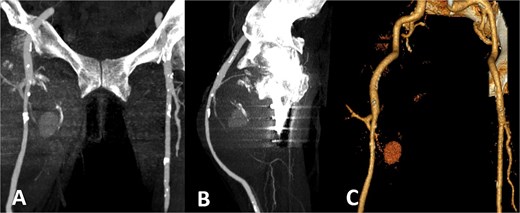

Colour duplex ultrasonography revealed a large heterogeneous mass measuring ~170 × 107 mm with partial thrombosis and residual arterial flow, consistent with pseudoaneurysm. Computed tomography (CT) angiography confirmed a large pseudoaneurysm arising from the profunda femoris artery and displacing the superficial femoral artery anteriorly (Fig. 3).

CT angiography. Large pseudoaneurysm (~170 × 107 mm) arising from the profunda femoris artery with partial thrombosis. The mass displaces the superficial femoral artery anteriorly. (A) Coronal CT image; (B) sagittal CT image; (C) three-dimensional reconstruction.